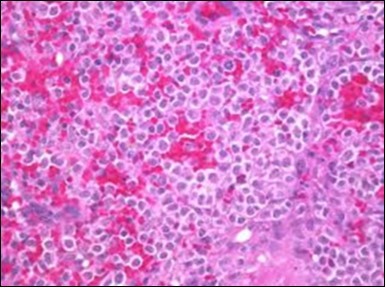

Figure 6.HCL: disseminated hairy cells with a clear cytoplasm(22).

The classic hairy cell is medium sized with a magnitude of 10-14µm. The moderately abundant or variable cytoplasm may be transparent or mildly basophilic. The cellular surface with the characteristic serrated perimeter depicts innumerable fragile or stout extensions of cytoplasm ,particularly discernible on the phase contrast and electron microscopy. The cytoplasm may exhibit vacuoles with occasional azurophilic granules4. The nucleus may be elliptical or reniform, folded or indented with a coarse, reticulated or a finely dispersed chromatin and inconspicuous nucleoli along with infrequent mitosis. Bone marrow aspiration or bone marrow trephine biopsy may be inadequate for diagnosis in 30%-50% individuals4. The trephine sections of the bone marrow may depict a characteristic interstitial pattern of leukaemic infiltration. Generally the bone marrow is hyper-cellular, though it may be hypo-cellular in 10-15% individuals4. The leukaemia cell ingress may be diffuse or partial, although diffuse infiltration is frequent. The partial variety of leukaemic dissemination may be ineptly categorized with an indeterminate differentiation from the uninvolved marrow. The malignant insertions may initially emerge as miniature, undefined, cellular loci. The formalin fixed, paraffin embedded sections may elucidate a crystalline zone or a “halo” appearance of the cells with a circumscribed nucleus on account of the plentiful cytoplasm4. The cellular margins may be intertwined. Fixation of bone marrow smears with Zenker’s fixative may demonstrate a retracted cytoplasm of the hairy cells with a consequent disconnected structure. The bone marrow in the absence of a malignant process may be hypo-cellular or hyper-cellular. Reticulin stains may delineate an enhanced accrual of broad, dense reticulum fibres surrounding the aggregates of leukaemia cells with the fibrous circumlocution of individual malignant cell and fibrotic extensions into the abutting, uninvolved bone marrow4.

The leukaemia cells may enunciate a characteristic immune phenotype, crucial for a confirmatory diagnosis. The peripheral blood mononuclear B cell population may display a kappa or lambda light chain restriction. The phenotype of classic hairy cell leukaemia may be delineated by concurrent, immune reactive CD19+ CD20+,CD 11c+, CD25+, CD103+ and CD123+. An intensely immune reactive CD200+ and a non reactive CD27- antigen may be present2, 4. Evaluation of a trephine bone marrow biopsy and bone marrow aspirate may define the degree of tumour infiltration. A dry tap on account of prominent bone marrow fibrosis may be elucidated at preliminary diagnosis. A decline in the normal haematopoiesis may account for a hypo-cellular marrow in 10% instances. Gradation of cellular infiltrating of the leukaemia within the bone marrow may be appropriately investigated with immune –histochemical stains2, 4. Immune staining for CD20+, annexin 1 and VE1 (a BRAF V600E stain] may validate the diagnosis and precisely analyse the extent of malignant bone marrow infiltration[8]. Determination of BRAF V600E mutation may be critical in therapeutically non responsive individuals with applicable standard therapy or in instances of multitudinous reoccurrences[9]. Deploying inhibitors of BRAF V600E gene may be efficacious in patients impervious to approved therapy. The mutation necessitates a comprehensive scrutiny of the implicated individuals with a sensitive molecular assay which may discern up to < 10% of the hairy leukaemia cells appearing in the peripheral blood smears or bone marrow aspirates diluted with peripheral blood or aspirates elucidating a dry tap[2,4]. Allele specific polymerase chain reaction (PCR) or a next generation sequencing may be optimally employed to circumvent false negative outcomes. If the leukaemia cells are sparse or if particularly sensitive & efficacious molecular techniques are not accessible, the application of appropriate immune histochemical stains to the bone marrow biopsy such as a BRAF V600E mutation stain (VE1) may detect the hairy cells and conclusively diagnose the condition[2,4,10]. Figure 1, Figure 2, Figure 3, Figure 4, Figure 5, Figure 6, Figure 7, Figure 8, Figure 9, Figure 10, Figure 11, Figure 12, Figure 13, Figure 14.